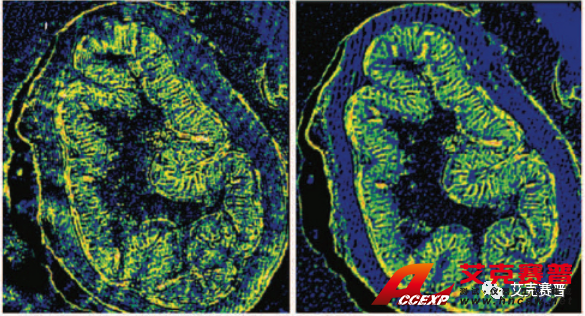

圖2顯示了布魯克已獲得專利的空間相干性抑制技術在采集激光紅外圖像時起到的改善作用。在左側的圖a和圖c中,可以看到激光束的干涉條紋對成像結果的影響。圖像看起來很模糊,有條紋和斑點。右側的圖b和圖d中相干性抑制技術在光源處消除了空間相干現象,從而采集到無比清晰的圖像(未經任何后期處理)。

圖2:布魯克的空間相干性抑制專利技術改善了使用QCL成像技術采集的紅外成像的質量: 我們得到了(d)原本的紅外成像圖,而不是(c)中干擾的傷偽影、條紋和斑點I2,該成像未經任何后期處理。